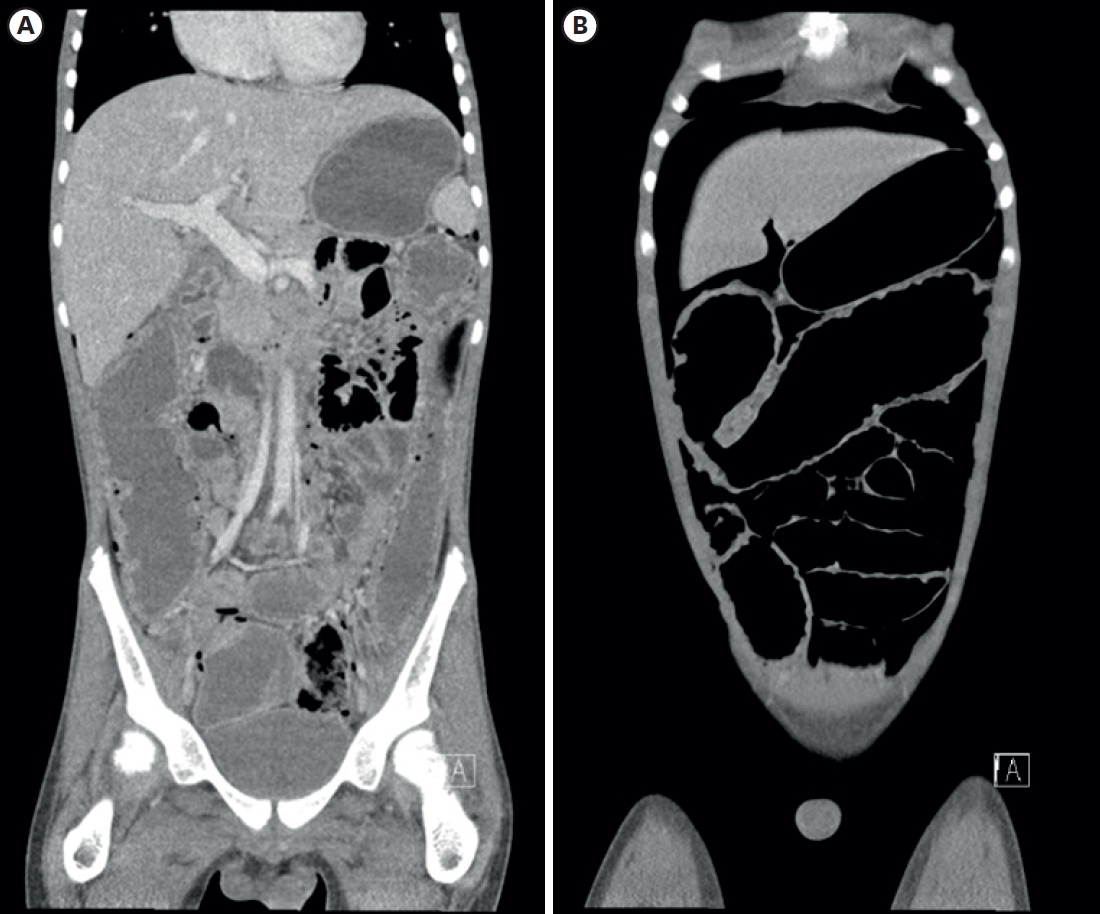

Pathological examination of the colon (Fig. 2) showed diffuse segmental mucosal ischemia with multiple undermining ulceration (Fig. 2A) and perforation along with submucosal and subserosal congestion. However, the distal resection margin was confirmed as viable, indicating rectal sparing. Defects in the intestinal wall were observed in areas presumed to be transverse and descending colons. Contrary to the preoperative diagnosis, no clear finding indicative of UC was noted. Although there were ulcers throughout the resected colon, their extension into the muscularis propria was thought to be incompatible with UC. Lack of cryptitis (Fig. 2B) and extreme plasmacyte-dominant lymphocyte infiltration (Fig. 2C and D) also contradicted UC. Extremely enlarged lymph nodes (Fig. 2E) and atypical lymphocyte aggregation (Fig. 2F) were notable. These were later determined to be macrophages by CD68 staining. T-cell receptor (TCR) rearrangement analysis showed monoclonality within a lymph node but not in the bowel infiltration. These additional immunohistochemistry and TCR clonality results led to the conclusion of a low possibility of malignant lymphoma, although there were scattered atypical cell infiltrations in both bowel and lymph nodes. A blood test performed on the 12th postoperative day found no evidence of cytopenia or hyperuricemia indicative of tumor lysis syndrome. IC was finally suggested as the cause of perforation. The patient was discharged. He showed no other signs of malignancy or IBD up to 11 months after surgery.

Fig. 2.

Gross and histologic findings. (A) Undermining ulceration of the colon. (B) Histopathologic findings of colonic ulceration (H&E stain, ×40). Black triangles indicate undermining ulceration, and arrows indicate preserved crypt architecture and absence of chronic mucosal distortion. (C) Extreme lymphoid infiltration. (D) Atypical lymphocytes found within lymphoid infiltration. (E) Sinus histiocytosis of lymph node. (F) CD68 immunohistochemistry staining shows infiltration of atypical cells in a lymph node.

H&E, hematoxylin and eosin.

Fig. 2. Gross and histologic findings. (A) Undermining ulceration of the colon. (B) Histopathologic findings of colonic ulceration (H&E stain, ×40). Black triangles indicate undermining ulceration, and arrows indicate preserved crypt architecture and absence of chronic mucosal distortion. (C) Extreme lymphoid infiltration. (D) Atypical lymphocytes found within lymphoid infiltration. (E) Sinus histiocytosis of lymph node. (F) CD68 immunohistochemistry staining shows infiltration of atypical cells in a lymph node. H&E, hematoxylin and eosin.